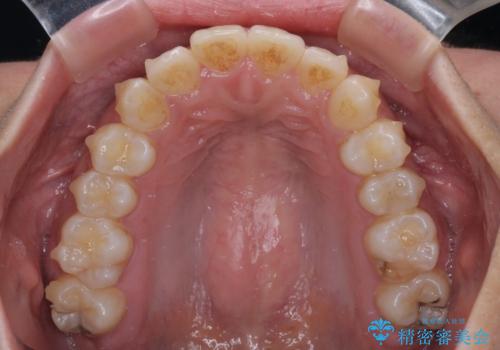

前歯のデコボコと隠れてしまう下顎前歯 インビザラインですっきりと改善

- 前歯のデコボコと、深い咬み合わせにより前歯が隠れていることを気にして来院された患者様です。

海外に長期滞在する予定があるとのことで、インビザラインにて矯正治療を行うこととしました。

インビザライン発注後に長期滞在先から2年間ほど帰国することができず、インビザラインの有効期限内に終了できるのか不安でしたが、矯正治療開始後は十分な装着時間を達成され、1年未満の期間で無事に終えることができました。